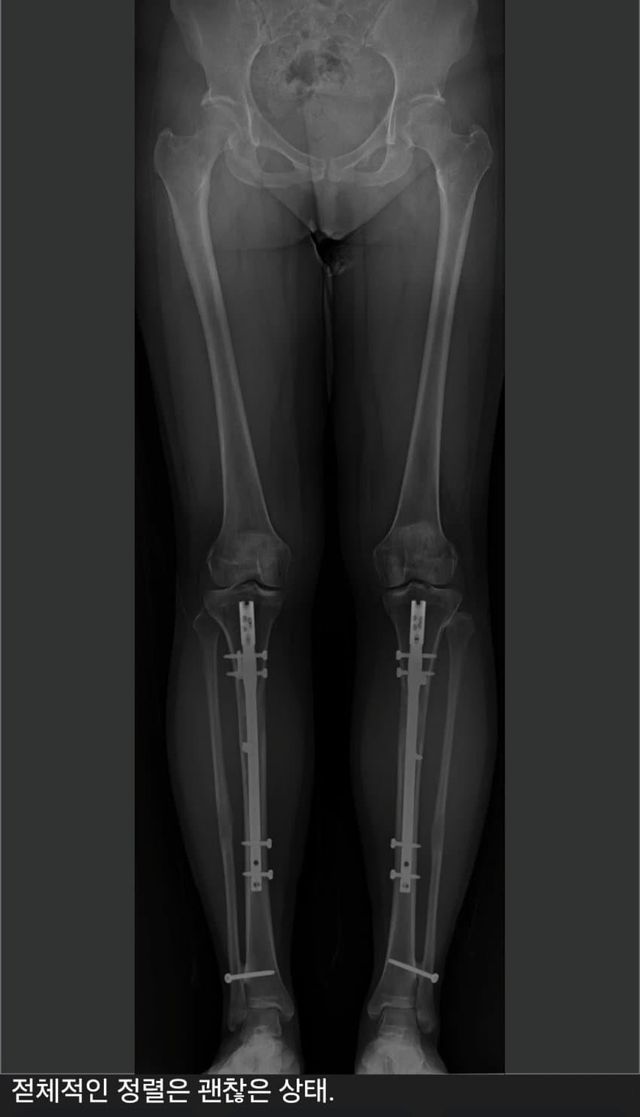

1. 6cm 늘림

2. 다리 아픔

3. 3.5cm 줄임